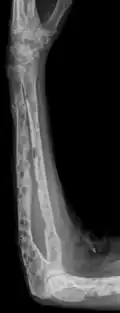

The diagnostic examination of a person with suspected multiple myeloma typically includes a skeletal survey. This is a series of X-rays of the skull, axial skeleton, and proximal long bones. Myeloma activity sometimes appears as "lytic lesions" (with local disappearance of normal bone due to resorption) or as "punched-out lesions" on the skull X-ray ("raindrop skull"). Lesions may also be sclerotic, which is seen as radiodense.[76] Overall, the radiodensity of myeloma is between −30 and 120 Hounsfield units (HU).[77] Magnetic resonance imaging is more sensitive than simple X-rays in the detection of lytic lesions. An MRI may supersede a skeletal survey, especially when vertebral disease is suspected. Occasionally, a CT scan is performed to measure the size of soft-tissue plasmacytomas. Nuclear Medicine Bone scans are typically not of any additional value in the workup of people with myeloma (no new bone formation; lytic lesions not well visualized on nuclear bone scan).

X-ray of the forearm, with lytic lesions -

Femur with multiple myeloma lesions -

Same femur before myeloma lesions for comparison -

Humerus with multiple myeloma lesions -

Same humerus before, with just subtle lesions